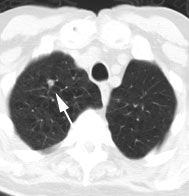

Metastatic head and neck cancer with secondary lung malignancy: The patient shown below had a history of head and neck cancer. The PET scan demonstrated a metastatic lesion to the right temporal bone. Also noted was intense uptake in the right lung apex(black arrow below right)- on CT this was felt to represent scarring (black arrowhead). FDG uptake is highly suggestive of a separate primary lung cancer. |